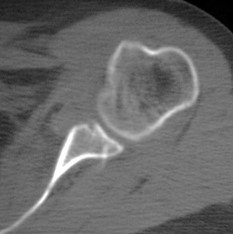

22-year-old basketball player has recurrent instability despite #labral repair two years ago. What is happening here, and how would you manage him now?

#LearnwithAAOS online learning programs and self-assessment and earn #CME and #SAE for #MOC bit.ly/2IIlLV7

#orthopedic